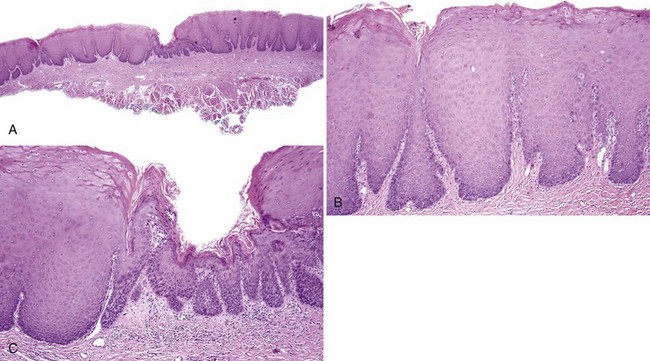

Гистопатология

Гистологически лейкоплакии полости рта проявляются как гиперкератоз, легкая дисплазия, умеренная дисплазия, тяжелая дисплазия или карцинома in situ. Дисплазия включает изменения архитектурных особенностей, а также цитологических особенностей ткани.Архитектурные особенности дисплазии включают асимметричное расслоение эпителия, повышенное количество митотических фигур в эпителии, дискератоз, каплевидные сетчатые стержни и кератиновые жемчужины внутри этих сетчатых стержней, потерю полярности базальных клеток и гиперплазию базальных клеток или анаплазию. В то время как цитологические особенности включают ядерный плеоморфизм, клеточный плеоморфизм, увеличение ядерно-цитоплазматического соотношения, заметные ядрышки и гиперхромазию. [14] Классификация легкой, средней и тяжелой дисплазии применяется, когда эта архитектурная и цитологическая атипия затрагивает менее одной трети, от одной трети до двух третей и более двух третей эпителия, соответственно.Карцинома in-situ — это термин, используемый, когда задействована вся толщина эпителия, при котором дисплазия распространяется от базального слоя до вышележащей слизистой оболочки, не вторгаясь в подлежащую соединительную ткань [15].